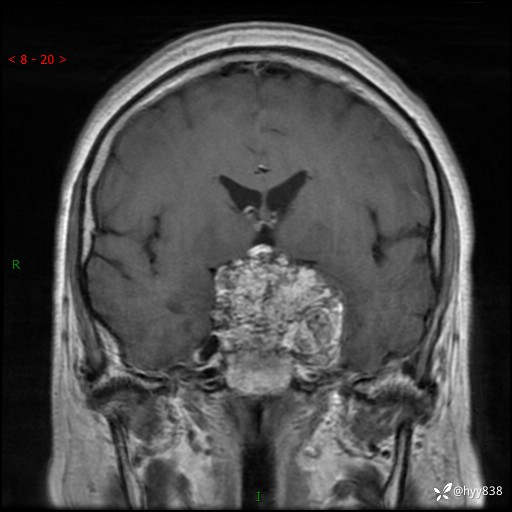

鞍区MRI平扫

T1WI cor

增强 COR +SAG